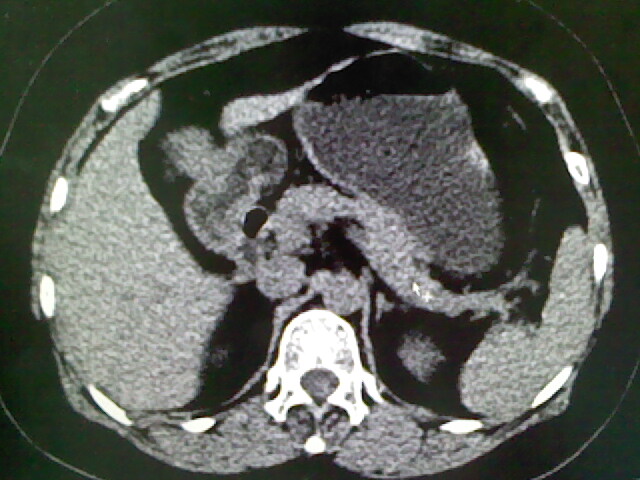

以下是引用卜一在2009-4-2 13:26:00的发言:[br]胆囊颈部结石伴胆囊炎!另:建议增强,待除外肝内占位及胆囊占位!

以下是引用liaoqiang在2009-4-2 16:23:00的发言:[br]胆囊是否切除?胆囊颈区致密影考虑金属夹?结石?肝脏右叶低密度影,考虑增强。